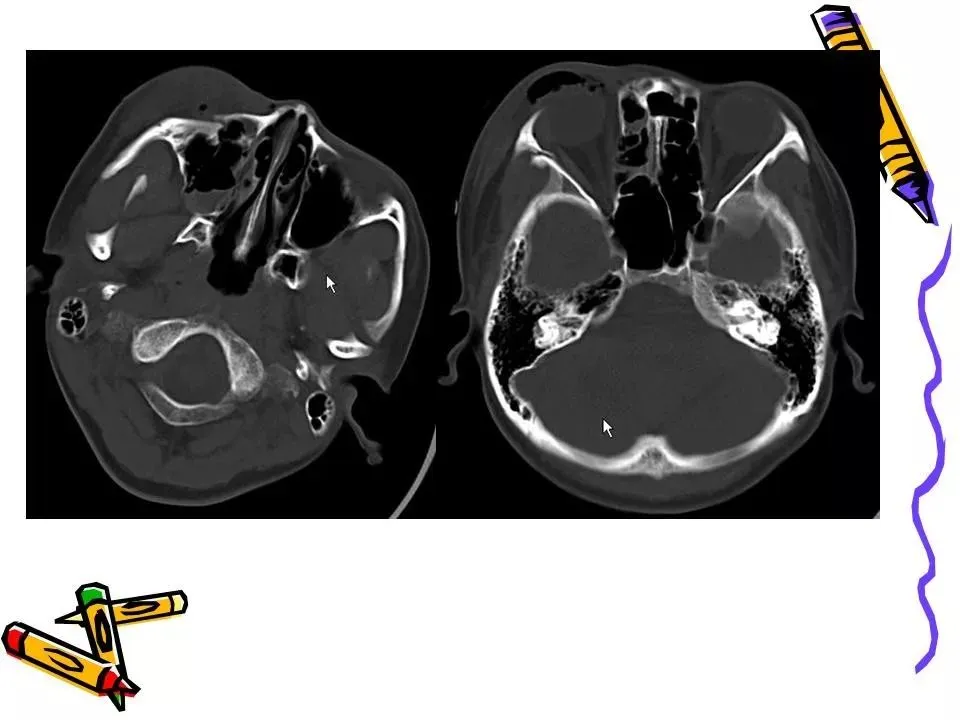

>常见颅脑外伤CT诊断(PPT)

常见颅脑外伤CT诊断(PPT)